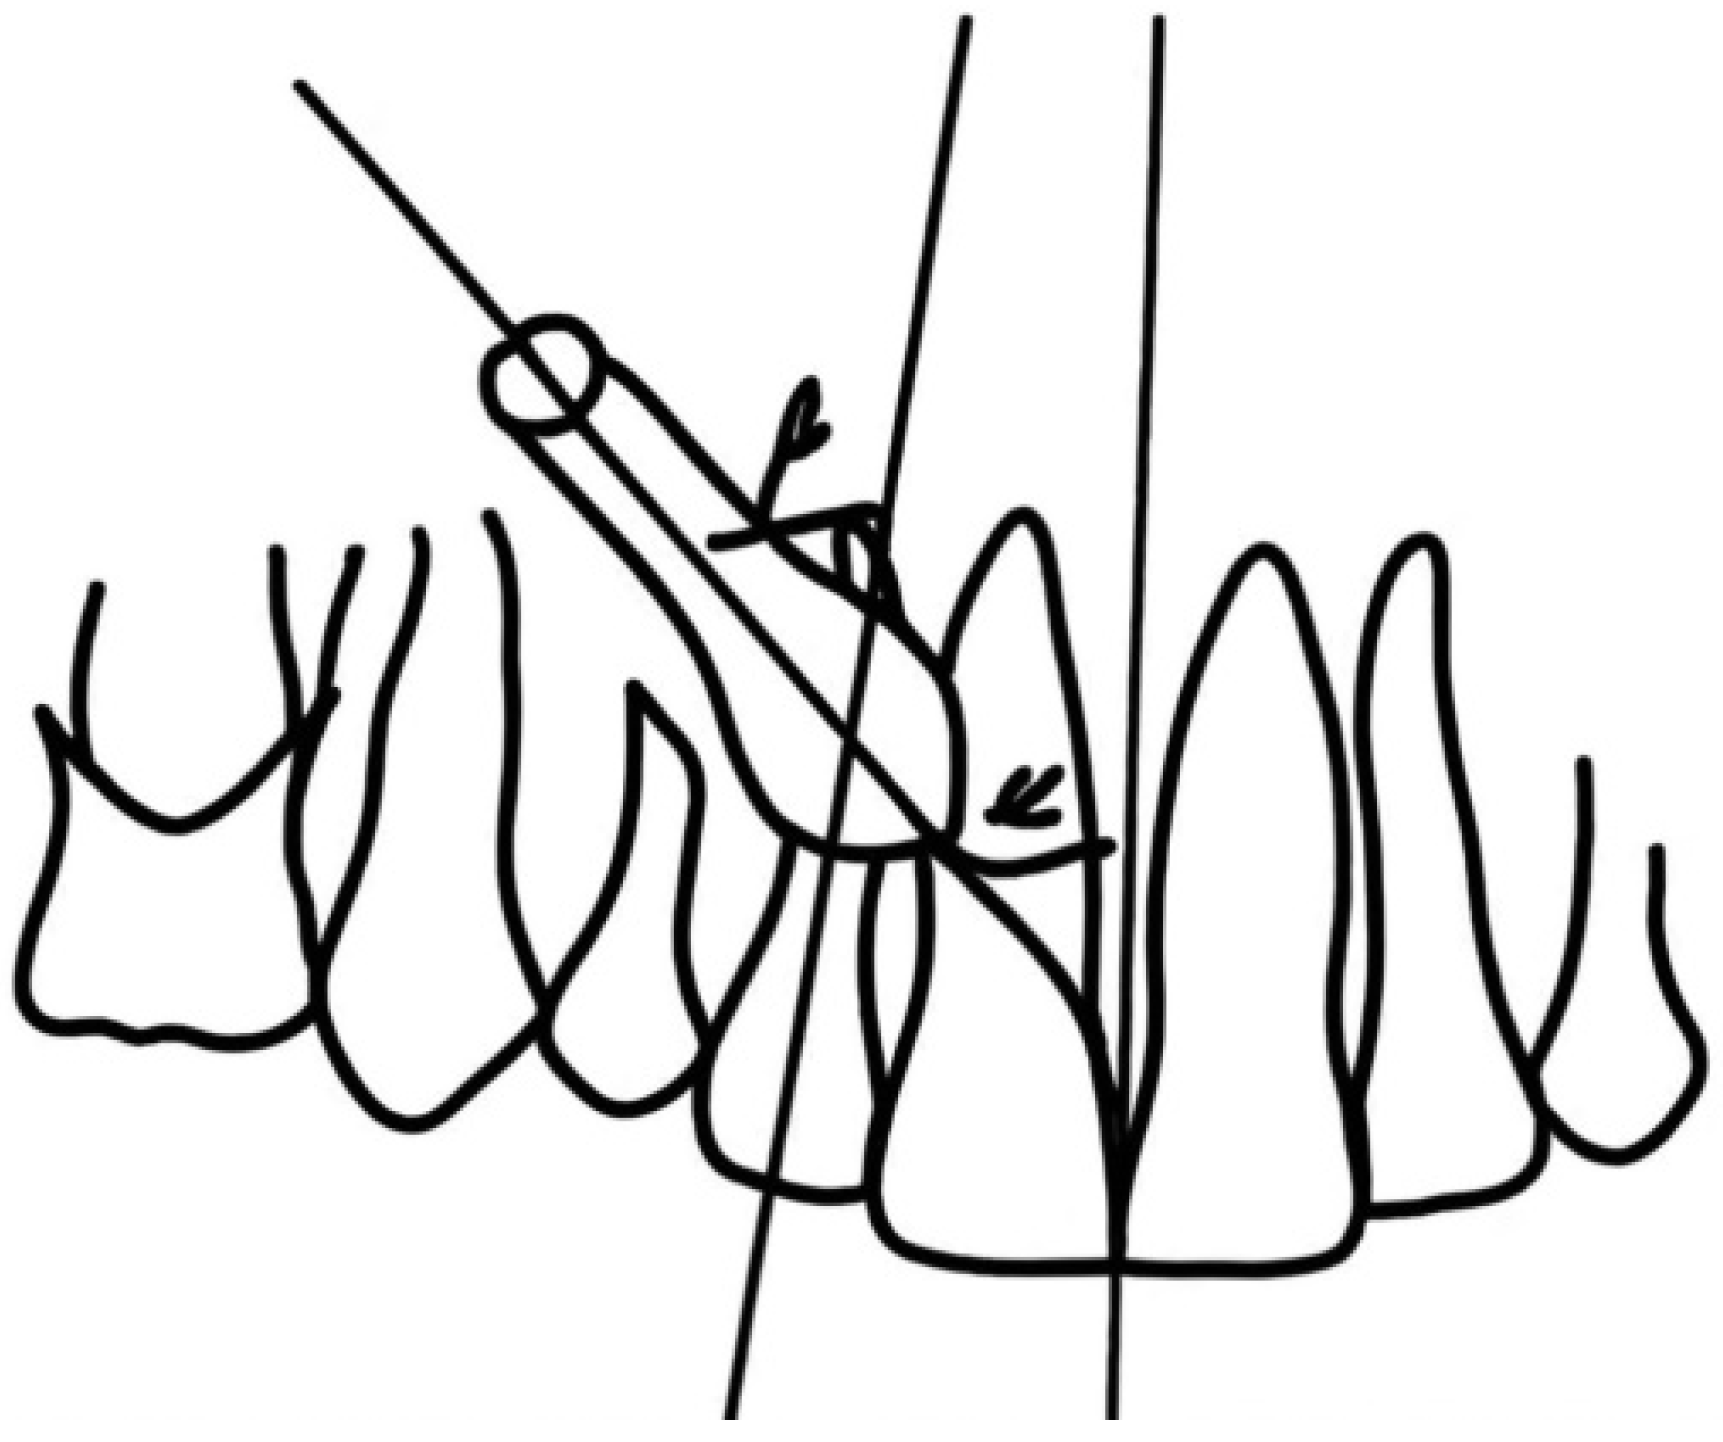

Two-Dimensional Radiographic Diagnosis of Maxillary Canine Impactions

2.2. Data Collection

2.3. Data Analysis